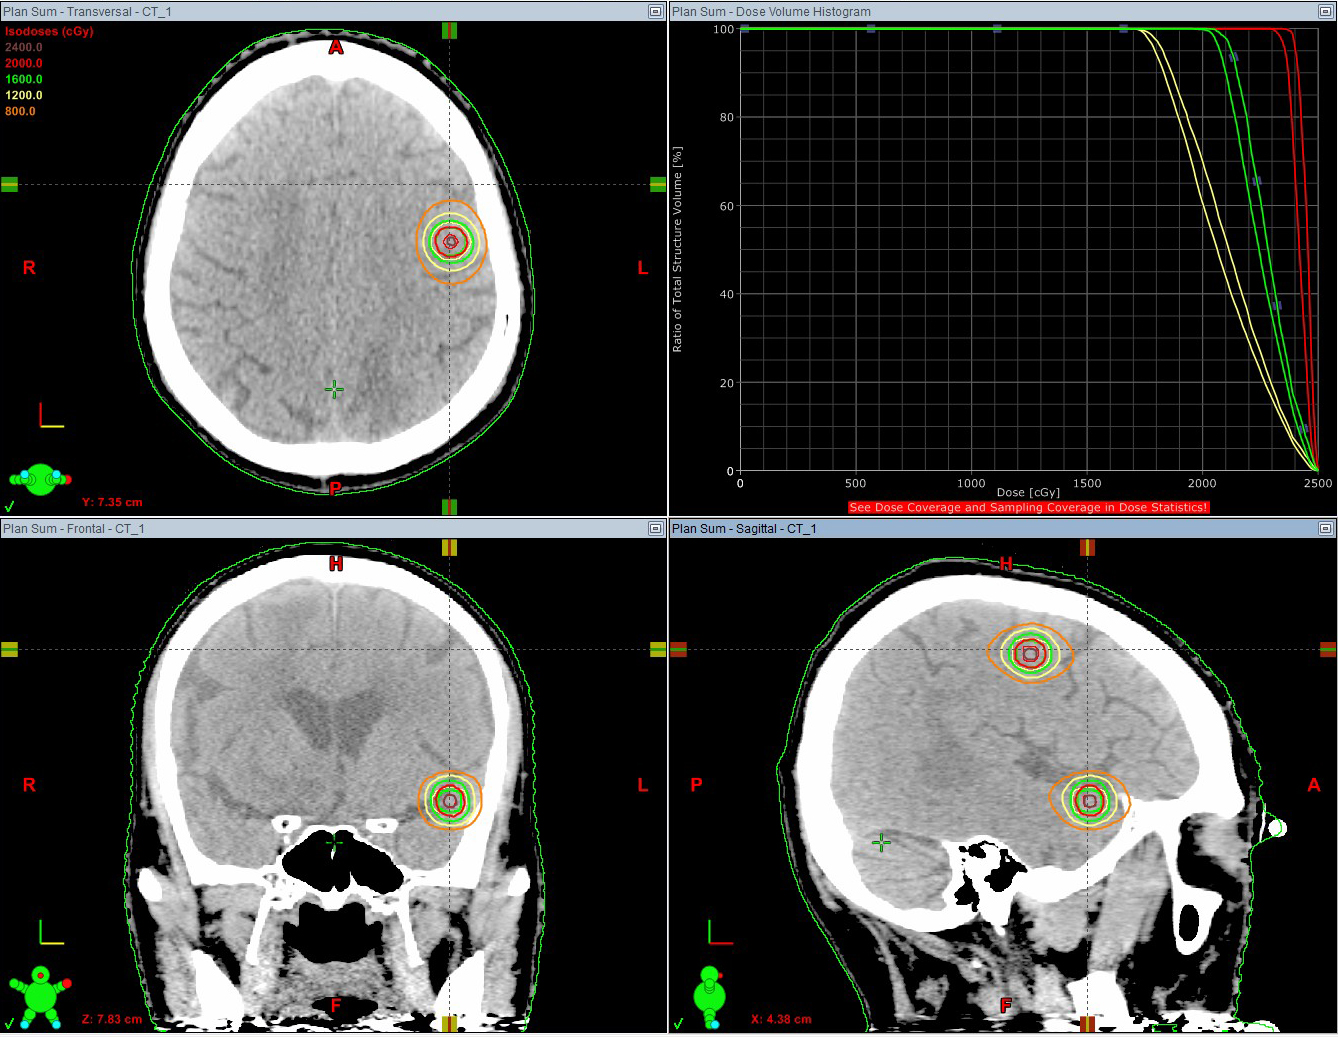

![]() 2017年11月,71歳男性 肺癌脳転移(2カ所),20Gy/1回 |